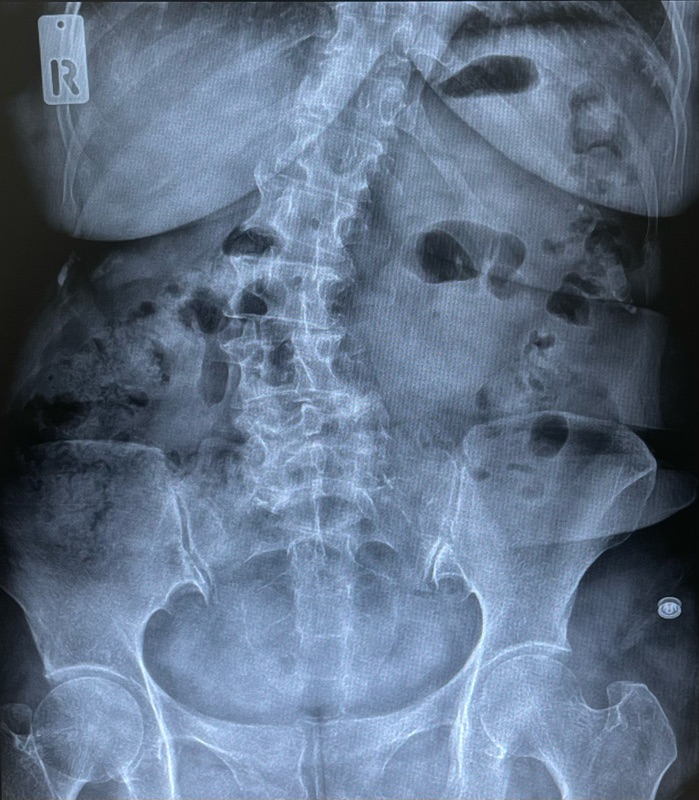

2) เอกซเรย์เต็มยืน (Full standing X-ray)

จำเป็นมากเพื่อดูองศาความคด (Cobb’s angle) และความสมดุลของลำตัว